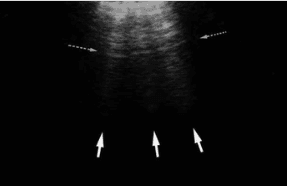

Z lines are hyperechoic lines extending from the pleural line that can sometimes be mistaken for B line but are a common finding in normal lungs. There is no clinical significance to Z lines.